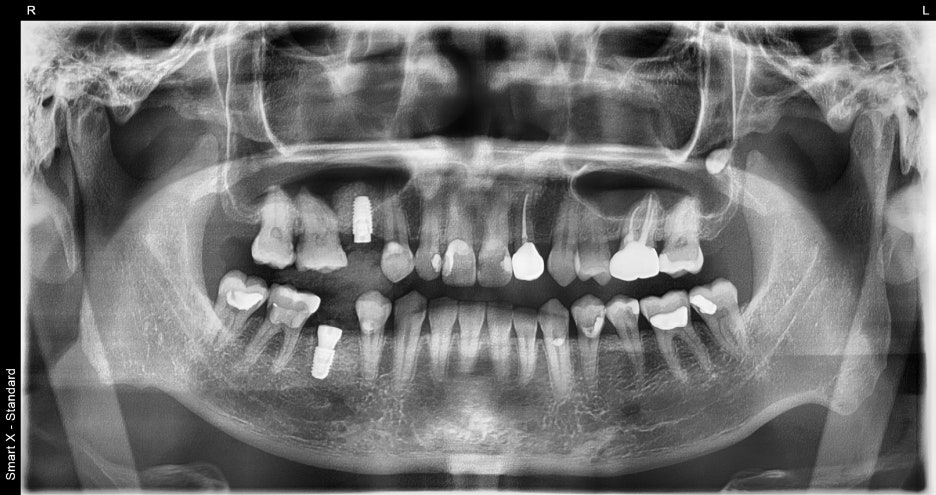

② Implant placement

– We also placed an implant simultaneously in the missing area. Because the bone condition was good, placement was possible stably

without additional procedures.

④ Final prosthesis placement

– In the in-house dental laboratory, we fabricated and placed a zirconia crown tailored to the patient’s bite and tooth color. After placement, bite adjustment was performed to distribute chewing force evenly on both sides.

1st visit: #45 extraction + immediate implant,

#15 implant placed simultaneously

2nd–3rd visits: Healing and osseointegration check

4th visit: Final prosthesis placement

→ Total of about 3 months, completed in 4 visits